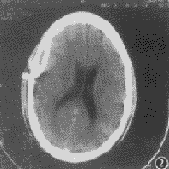

图1 右额、颞顶部硬膜下积脓、右颞部脑水肿、右侧脑室受压,中线结构左移1.8~2.0 cm,脑底池变窄、欠清,两侧裂及脑沟不清,脑回增粗。